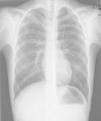

Caso n.° 2: niño de 11 años con mielomeningocele, portador de una DVPL durante 5 meses, que había presentado una neumonía 2 meses antes (fig. 2), con mejoría clínica tras recibir antibiótico, pero con reaparición intermitente de la fiebre al suspenderlo. El paciente presentó cefalea y pérdida de visión 24h antes del ingreso, objetivándose una fístula cutánea en la zona del reservorio. La analítica presentaba 14.400 leucocitos/μl (neutrófilos 56%), PCR de 10,6mg/dl y VSG de 79mm, decidiéndose la externalización del catéter. El LCR presentaba 230 leucocitos/μl (10% neutrófilos), aislándose repetidamente Corynebacterium spp. (inicialmente interpretado como contaminación) sensible a penicilina. Los hemocultivos y el cultivo del catéter fueron estériles. Se inició tratamiento con vancomicina, sustituyéndose posteriormente por ampicilina. A pesar de ello, los cultivos persistieron positivos, por lo que se retiró la derivación y se colocó un drenaje externo. Tras 10 días con LCR estéril, se reimplantó una derivación ventrículo-auricular, manteniéndose el antibiótico 15 días más, con buena evolución.

Existe poca bibliografía sobre las infecciones de DVPL, pudiendo cursar con derrame pleural, empiema o neumotórax6,9. La neumonía inicial del segundo paciente fue consecuencia de la infección pleural desde el DVPL.